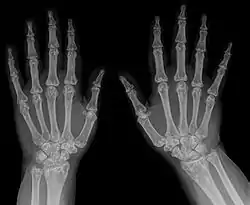

- الأشعة السينية

| التشخيص | أشعة سينية، والموجات فوق الصوتية[2] |